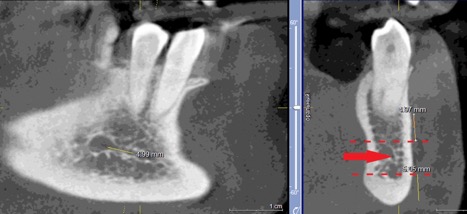

При измерении расстояния от резцовой петли до вестибулярной стенки нижней челюсти и её топографии в области правила «трёх пятёрок», выделено три положения канала, в котором проходит резцовая петля: канал прилежит, т.е. стенка канала образована кортикальной частью (рис 3), касается, т.е. имеет одну общую точку (рис 4) и не имеет общих точек.

Рисунок 3. КЛКТ Сагиттальный и коронарный реформаты переднего отдела нижней челюсти.

Стенка канала образована кортикальной частью кости.

Красная стрелка – «резцовая петля».

Красный пунктир – канал проходит в проекции участка правила «трёх пятёрок».

Рисунок 4. КЛКТ Сагиттальный и коронарный реформаты переднего отдела нижней челюсти.

Канал соприкасается с кортикальной частью кости (красная стрелка – резцовая петля).